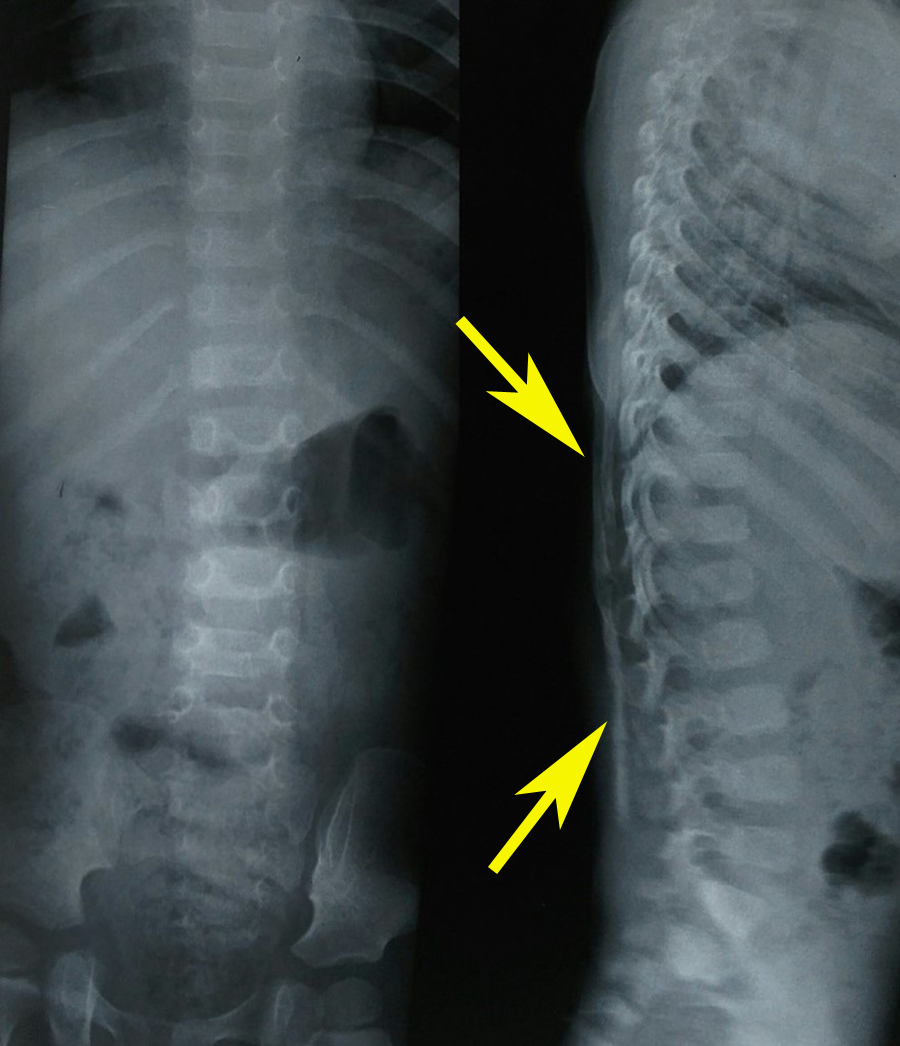

Physical examination revealed bilateral shortening and valgus deformity of the great toes (Figure 1). Multiple swellings of variable size were present on occiput, nape of neck, bilateral scapular area, bilateral axilla and midback. Swellings were non tender, hard, smooth, mobile with well-defined edges and were lying in subcutaneous tissues & muscles. Movements of the neck and bilateral shoulder were decreased (Figure 3). Rest of the joints including bilateral hips, elbows, wrists, knee, and ankle were normal. A radiograph of the right shoulder showed osteomas between the scapula and the proximal end of the humerus (Figure 4). Cervical spine radiographs revealed large posterior elements, narrow vertebral bodies and loss of cervical lordosis (Figure 5). Radiograph of the dorso-lumbar spine revealed large ectopic bone mass bridging the lower dorsal and lumbar spine (Figure 6). Radiograph of the knees revealed the presence of osteochondromas of the proximal medial end of the tibia (Figure 7). Lab findings were normal except for raised ESR (50mm in first hour) & liver enzymes were mildly raised. Patient was diagnosed as a case of FOP on the basis of clinico-radiological examinations. Biopsy was not done because of the fear of flaring up of the disease. Oral prednisolone was given in a dose of 2mg/kg for 5 days. Acute flare of the disease settled and the patient was discharged with advice of regular follow-ups.

Figure 6 Radiograph of the dorso-lumbar spine revealed large ectopic bone mass bridging the lower dorsal and lumbar spine (arrows).

While some flare-ups spontaneously regress, flare-ups can transform soft tissues (skeletal muscles, tendons, ligaments, fascia, and aponeuroses) into heterotopic bone. Newly formed bone (Figure 4 & 6) spans the joints, renders movement impossible.5,14 The natural history of this condition is characterized by inflammatory episodes of 2 to 3 weeks, with latency periods of several months in between. Ectopic skeletogenesis follows a specific anatomic configuration, involving the dorsal, axial, cranial, and proximal regions of the body first, followed by involvement of ventral, appendicular, caudal and distal regions later.1,6 The most common site for the onset of heterotopic ossification is the neck, with the spine and shoulder girdle being the next most common sites.1,4,6 Though heterotopic ossification in fibrodysplasia ossificans progressiva begins in childhood; but trauma such as minor soft tissue injury, muscular stretching, overexertion and fatigue, intramuscular injections and influenza-like illnesses can persuade flare-ups of the disorder. Loss of movements is accumulative and most patients are wheelchair bound by the end of the second decade. However, diaphragm, tongue, cardiac muscles, smooth muscles and extra-ocular muscles are spared from abnormal ossification.